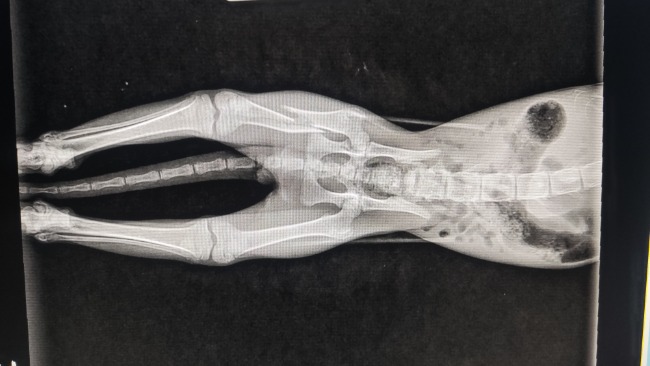

Ale czy mógłbyś mi podarować zdrową łapkę? Miałem wypadek, nie chcę wspominać jak bardzo mnie bolało. Ale teraz mam szansę. Tylko potrzebna jest droga operacja. A ja nie jestem bogatym kotkiem – właściwie to nie mam nic.

Malutki Maciuś został znaleziony z poharataną łapką. Potrzebuje szansy – operacji, hospitalizacji, czułości i opieki. Bardzo potrzebuje pomocy i domu :(